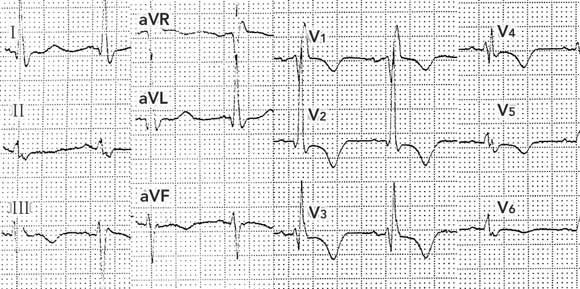

Review of the patient’s previous medical records revealed, on a thoracoabdominal image derived from computed tomography data, a foreign body in the central abdominal region (Box 2). Questioning of the patient after the angioplasty revealed that this was an electrostimulator (Itrel II, Medtronic, Minneapolis, USA) implanted a few years earlier as part of a dynamic graciloplasty to treat faecal incontinence. An ECG performed 12 hours after the angioplasty with the device deactivated (by the patient’s control programmer) produced an ECG tracing free of artefacts (Box 1B).

Persistent and inexplicable ECG artefacts should raise the suspicion of interference from a device generating high frequency electrical impulses. Such devices may include minute ventilation rate-responsive pacemakers1 and central or transcutaneous neurostimulators (eg, deep brain neurostimulators used in Parkinson’s disease,2 and spinal neurostimulators used in chronic back pain3). Occasionally, when the vector of impulses is perpendicular to an ECG lead, the tracing from that lead may be free of artefacts (eg,Box 1A, lead I).

Intrathoracic devices are usually discovered on physical examination or standard chest x-ray, but devices in other parts of the body may not be obvious. In dynamic graciloplasty to treat anal incontinence, the gracilis muscle is transposed around the anal canal and electronically stimulated by a device placed in a subcutaneous pocket in the abdominal wall.4 In our case, this device led to ECG artefacts potentially interfering with the ability to diagnose the acute myocardial infarction.